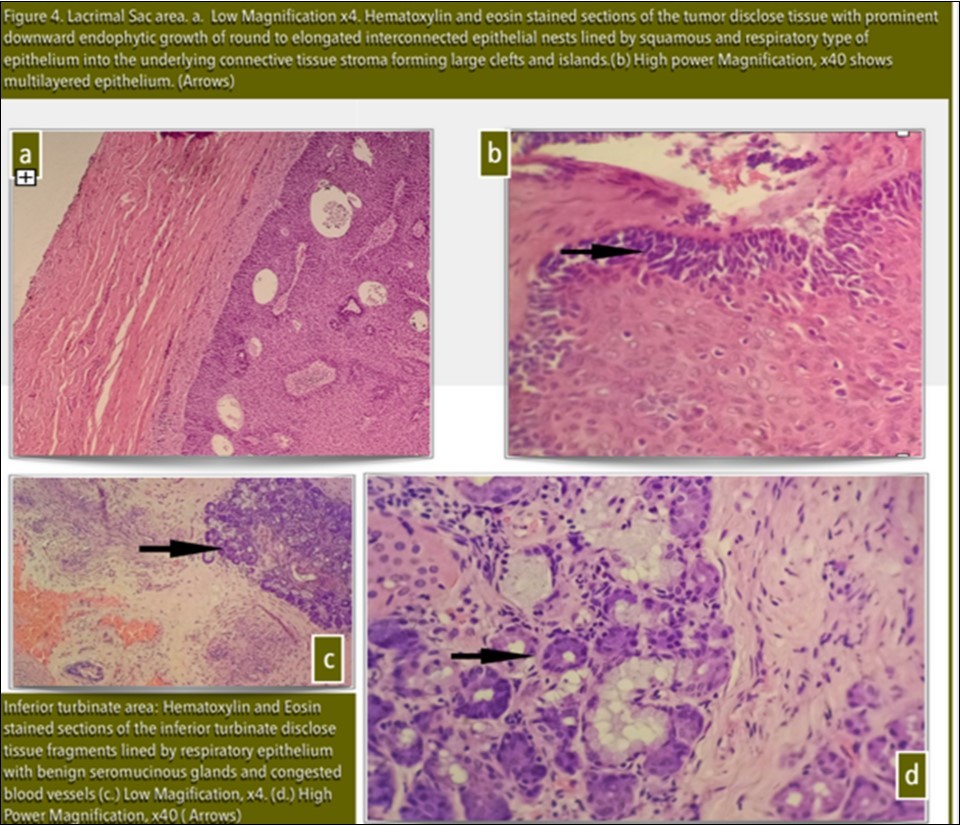

Histopathology results showed tissue fragments lined by squamous and respiratory epithelium with prominent downward endophytic growth of epithelial nests with intact basement membrane conclusive of Inverting Papilloma [Figure 4a, 4b, 4c and 4d].

Figure 4.Lacrimal Sac area. a. Low Magnification x4. Haematoxylin and eosin stained sections of the tumor disclose tissue with prominent downward endophytic growth of round to elongated interconnected epithelial nests lined by squamous and respiratory type of epithelium into the underlying connective tissue stroma forming large clefts and islands. (b) High power Magnification, x40 shows multilayered epithelium. (Arrows)